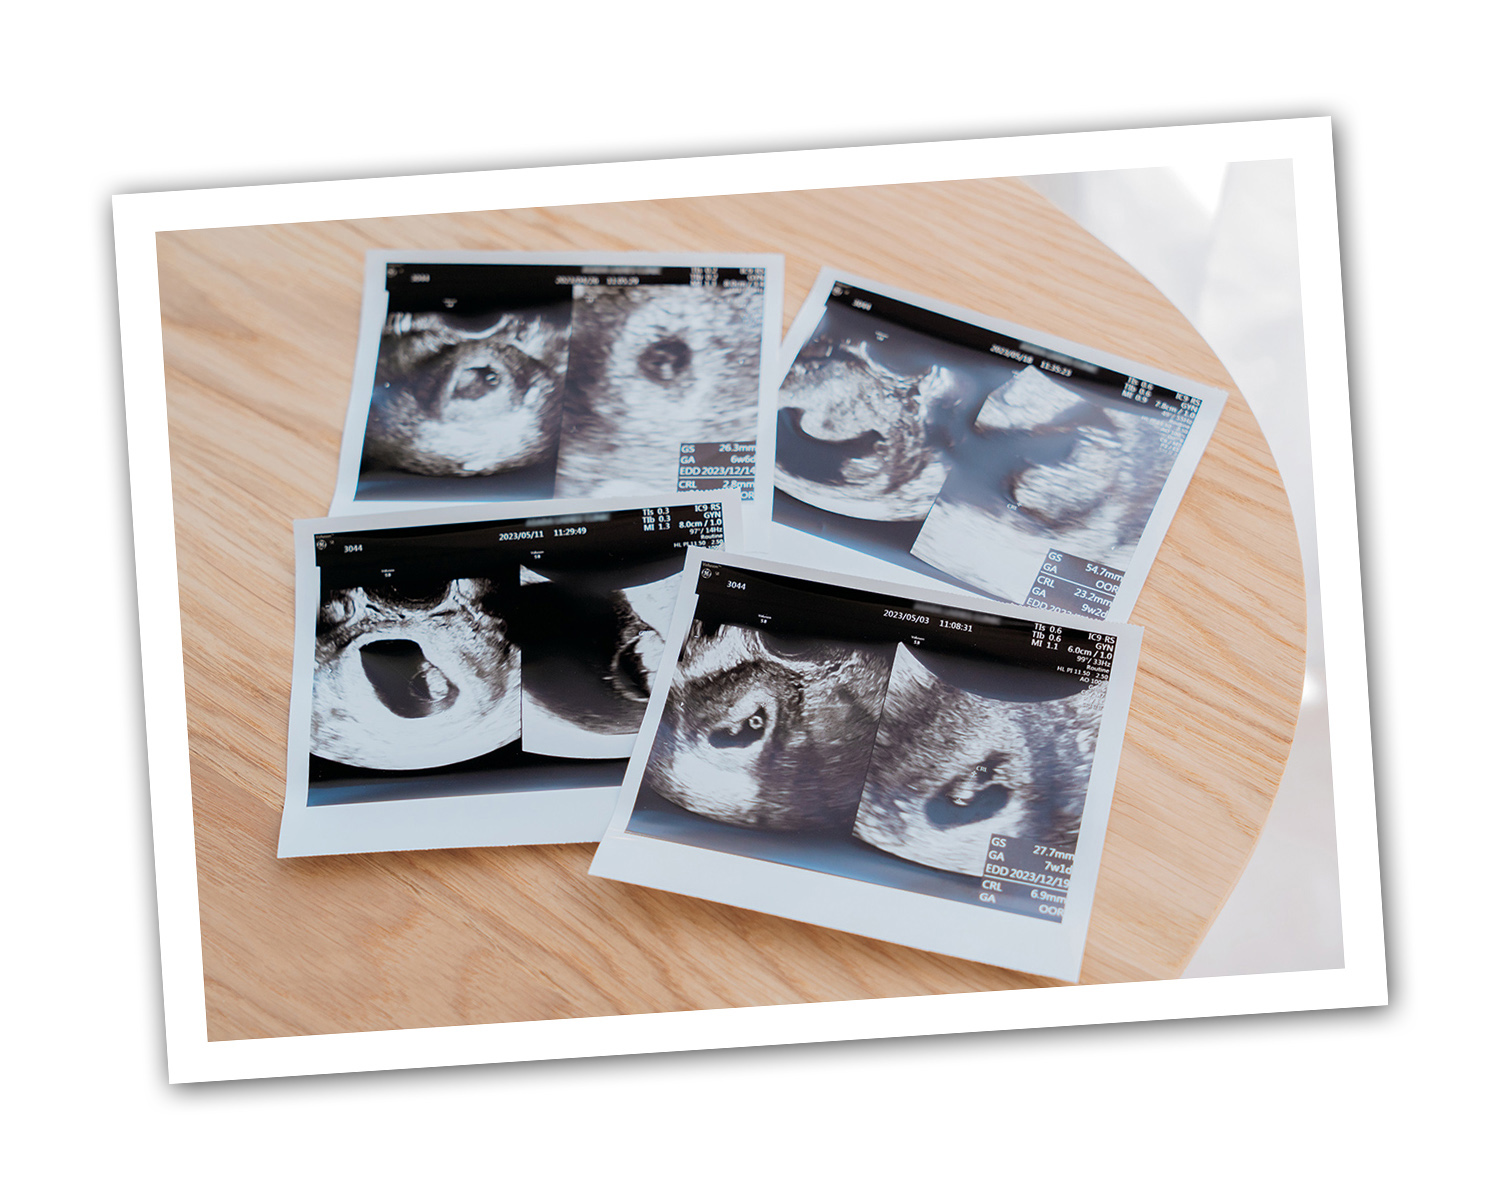

「妊娠してからは毎日ハラハラドキドキ。エコーで赤ちゃんが元気に育っていることを確認して安心していました」